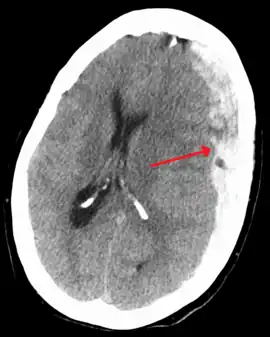

Chronic subdural after treatment with burr holes

Treatment of a subdural hematoma depends on its size and rate of growth. Some small subdural hematomas can be managed by careful monitoring as the blood clot is eventually resorbed naturally. Others can be treated by inserting a small catheter through a hole drilled through the skull and sucking out the hematoma.

Large or symptomatic hematomas require a craniotomy. A surgeon opens the skull and then the dura mater; removes the clot with suction or irrigation; and identifies and controls sites of bleeding.[28][29] The injured vessels must be repaired. Postoperative complications can include increased intracranial pressure, brain edema, new or recurrent bleeding, infection, and seizures. In patients with a chronic subdural hematoma but no history of seizures, it is unclear whether anticonvulsants are harmful or beneficial.[30]

Those with chronic subudural haematoma (CSDH) with few or no symptoms or have high risk of complication during surgery may be treated conservatively with medications such as atorvastatin, dexamethasone,[31] and mannitol, although supporting conservative treatment is still weak.[32] HMG-CoA reductase inhibitor such as Atorvastatin can reduce the haematoma volume and improving neurological function in eight weeks.[33] HMG-CoA reductase inhibitor may also reduce risk of recurrences in CSDH.[34] Dexamethasone, when used together with surgical drainage, may reduce the recurrence rate of subdural haematoma.[35] Even with surgical evacuation of chronic subdural haematoma, the recurrence rate is high, ranging from 7 to 20%.[32]